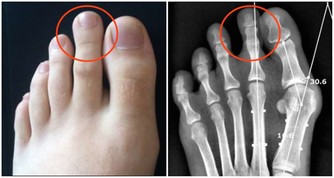

中指的三個指節不對稱,第二節特別長:鈣質的代謝較差,易患骨骼、牙齒方面的疾病。

無名指第二節與筋骨強弱有關:過長、指紋散亂、瘦弱,鈣質吸收較差,骨骼和牙齒較脆弱。